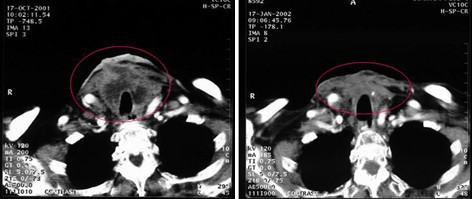

患者病情:鼻咽癌,左颈前、后两个淋巴结转移,大小近似,均为5.7cm2。治疗方案:前淋巴结接受放疗40Gy,后淋巴结注射今又生1×1012VP/次/周×4,联合40Gy放疗。治疗后,前、后淋巴结体积均缩小,前淋巴结缩小到2.9cm2,缩小40%;后淋巴结缩小到1 cm2,缩小72%,而且CT可见其内部空洞坏死,无癌细胞。

治疗前

治疗后